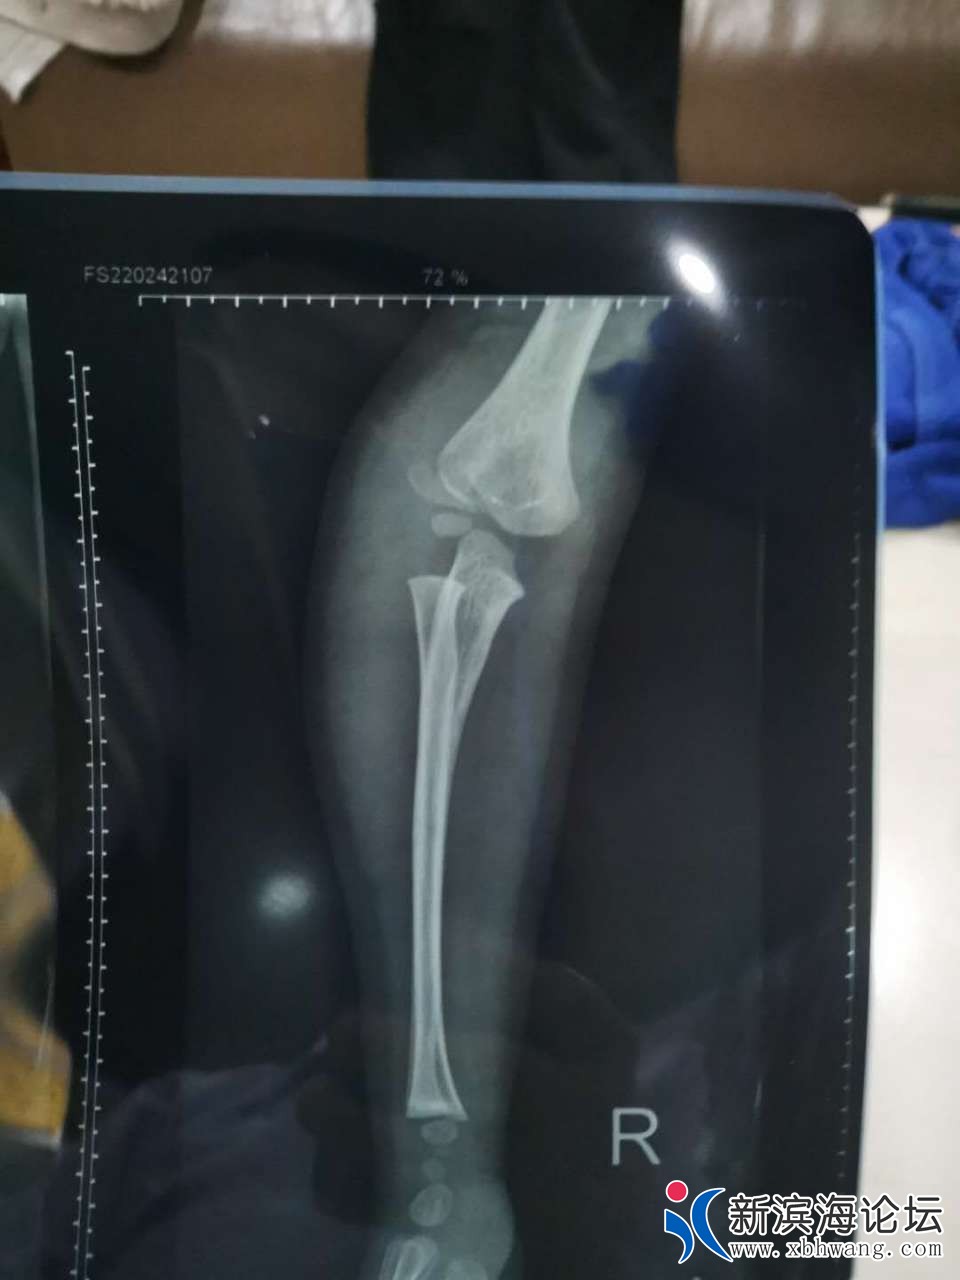

大家好 我是孩子的爸爸   3.31号晚  宝宝不小心从床上摔下来  家人比较担心  就带宝宝来到滨海第一人民医院就诊  挂完号我们等了很久才等到医生过来  简单两句话   就让我们去做血常规  再拍个片子  还嘱咐我们拍完 不用等片子出来   他可以从电脑上看  我们也不懂  就听了医生的话   等医生从电脑上看完片子  告诉我们说宝宝没有什么事  就是有点血肿  让我们回去冰敷一下就可以了  宝宝比较坚强  也没有哭  我们就相信了医生的话  带宝宝回家了  可是再到4.30号总觉得宝宝胳膊使不上力气  再次带着宝宝来到县医院复查  等来的结果却是骨折了  而且还要动手术  我们质疑了  因为3.31号晚上的片子  县医院有3个医生看过  都说没有问题   于是带着之前的片子和5月1号的片子来到其他几个医院   结果给我们的诊断都很肯定宝宝的胳膊骨折了   看过3月31号的片子  也都说  之前的片子就看的出来是骨折了  现在要动手术  而且还担心留下残疾    瞬间就感觉天塌下来了  很相信我们滨海的县级医院   结果给宝宝误诊了   现在已经一个月下来了     宝宝耽误了最佳治疗时期   滨海其他医院已经不接收这么小的宝宝 因为也错过了最佳治疗时间  我们再次来到县医院  想处理下宝宝现在的状况  可是 医院找各种理由  推脱      找到当日的值班医生  现在还不承认  说他没错  还让我们去骨科再看   真就不明白  来到医院  挂号  如果你看不了这个病  为什么让我们去做一系列的检查  还给我们诊断结果  说只是血肿  未见骨折现象     院方一味的找借口推脱  一副天不怕地不怕的样子  你们的良心不会痛吗   你们自己家里没有宝宝吗 以前总是在别人嘴里说县医院太差劲 这次,我们也算是真见到了  庸医  真的是害惨了我们一家人  特别是宝宝  他还4周岁不到  这么小  就遭这么大的罪   还有可能留下残疾的症状     真的就是黑心医院无良医生   也请有关上级领导帮忙彻查此次医疗事故  感谢不尽   下面附上宝宝两次拍的片子  前3张是3.31号晚上的   最后两张是5.1号的

你好,首先感谢你对我院工作的关心和支持,关于你反映的“县医院医生···”一事,我院高度重视,立即组织相关科室调查具体情况,患儿崔某某,男,4岁,因”意外伤"于2020年03月31日晚来我院急诊外科就诊,摄片见肱骨髁旁高密度影,考虑骨骺(小儿肘关节骨骺易与骨折混淆),初诊时不能明确,建议患儿家长三天后至我院骨科门诊复诊,患儿家长因为孩子肿痛不明显,未及时来院诊治,一个月后复查提示肱骨外科骨折,事情发生后,我院已经安排专人对接,目前正与患儿家长商讨下一步诊疗方案。最后再次感谢你对我院工作的关心和监督。